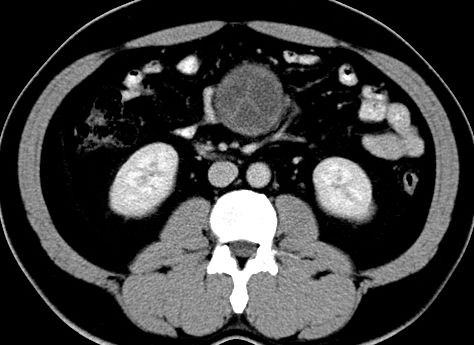

男,48岁,间断性下腹不适1年。

手术探查

:距回盲部28厘米处肠系膜根部可见5*7cm左右包块,质中等硬度,活动度尚可,肝、胆、胰、脾肾未见明显异常。

病理

:(腹腔)

神经鞘瘤

,伴出血、坏死及囊性变,伴淋巴结反应性增生。

免疫组化结果

:sma(-), desmin(-), cd117(-), s-100(+++), nf(-),vimentin(+++).